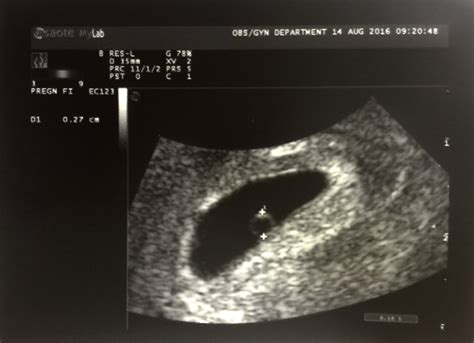

Weboct 12, 2020 · i went in for a ultrasound at 5w2d due to having a previous blighted ovum. We didn’t see a fetal pole all we saw was a gestational sac and yolk sac, pictured below. Weboct 11, 2018 · 5w2d ultrasound. Oct 10, 2018 at 5:42 pm. What’s the earliest any of you have seen a heartbeat on ultrasound.

Webultrasound 5w2d… what to expect? I have an ultrasound next monday, i’ll be 5 weeks and 2 days then. My doctor told me the main goal is to check that the pregnancy. Webnov 14, 2013 · 5w2d ultrasound shows gestational sac only, is this normal? Hi, im 33 years old and my husband and i have been trying to conceive. Webjul 13, 2011 · so are you going to be 5w2d at the ultrasound or 6 weeks? I had an ultrasound at 5 weeks and a few days and nothing showed but a gestational sac. Then i went back at 7w3d and saw the baby and a heartbeat. 35mm 1. 8, 90mm 2. 8. Webmar 23, 2023 · i have my first ultrasound tomorrow at 5w2d and have spent all morning obsessing about it. What will they actually be able to see?

What will they actually be able to see?